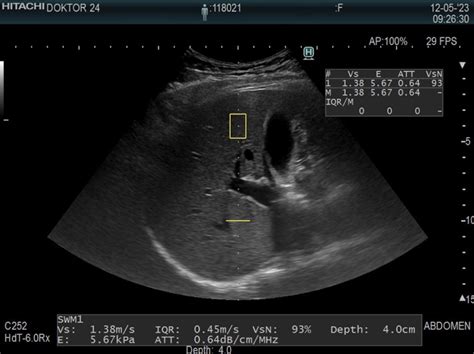

Policistični jajčniki (PCO) se nanašajo na stanje, pri katerem je v jajčnikih prisotno večje število manjših foliklov, ki se občasno ali v vsakem ciklu ne razvijejo v vodilni folikel in ne pride do ovulacije. To stanje se lahko opazi na ultrazvoku, vendar samo po sebi običajno ne povzroča neplodnosti ali drugih izrazitih znakov obolenja.

- Večje število foliklov na jajčnikih (PCO): Kot že omenjeno, se na ultrazvoku opazi večje število manjših foliklov.